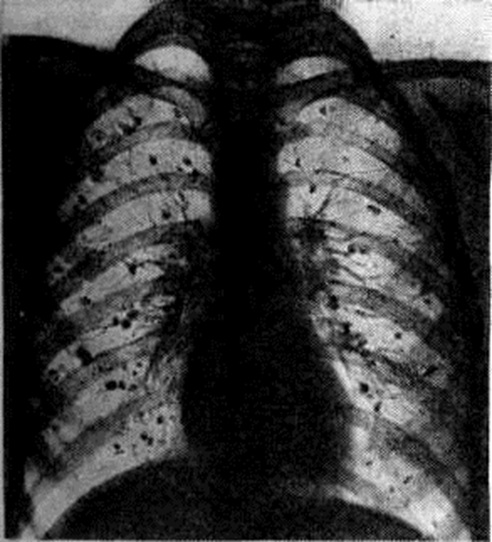

Рис. 4.

Рентгенограмма грудной клетки больного гистоплазмозом лёгких в стадии излечения. Милиарная кальцинация лёгких.

Первичный Гистоплазмоз лёгких у 80% инфицированных протекает бессимптомно. Первичный лёгочный комплекс по величине и форме очень похож на первичный туберкулёзный комплекс, выявляется в виде небольшого ограниченного субплеврального очага чаще всего в нижней и средней долях лёгких. Первичный Гистоплазмоз лёгких распознается обычно лишь методом внутрикожной пробы с гистоплазмином; но, несмотря на бессимптомное течение, у многих больных через 3—5 лет в лёгких (рисунок 4) развиваются множественные мелкие кальцинаты (обызвествление бугорков), иногда обнаруживаемые в печени и селезёнке. У 20% инфицированных первичный Гистоплазмоз лёгких сопровождается общими симптомами различной тяжести.